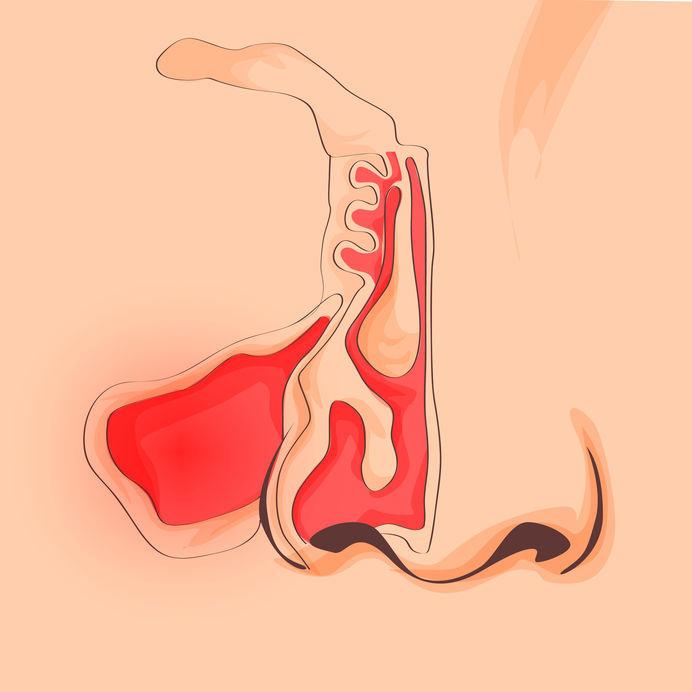

Alergiile respiratorii apar când sistemul imunitar reacționează exagerat la particule care, în mod normal, nu sunt dăunătoare: polen, mucegai, praf, păr de animale sau anumite substanțe din mediul casnic. Simptomele frecvente includ strănut, mâncărime nazală, congestie, secreții nazale, tuse, senzație de presiune facială și ochi roșii sau lăcrimători.

Alergiile respiratorii implică două componente majore: expunerea la alergen și răspunsul imun mediat de anticorpi sau celule inflamatorii. Tratamentul convențional urmărește reducerea simptomelor și modificarea răspunsului imun prin evitare, medicamente simptomatice și, uneori, imunoterapie specifică.